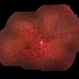

- peripheral ischemia

- Imaging device

- Fundus camera

- Peripheral ischemia by angiography with montage